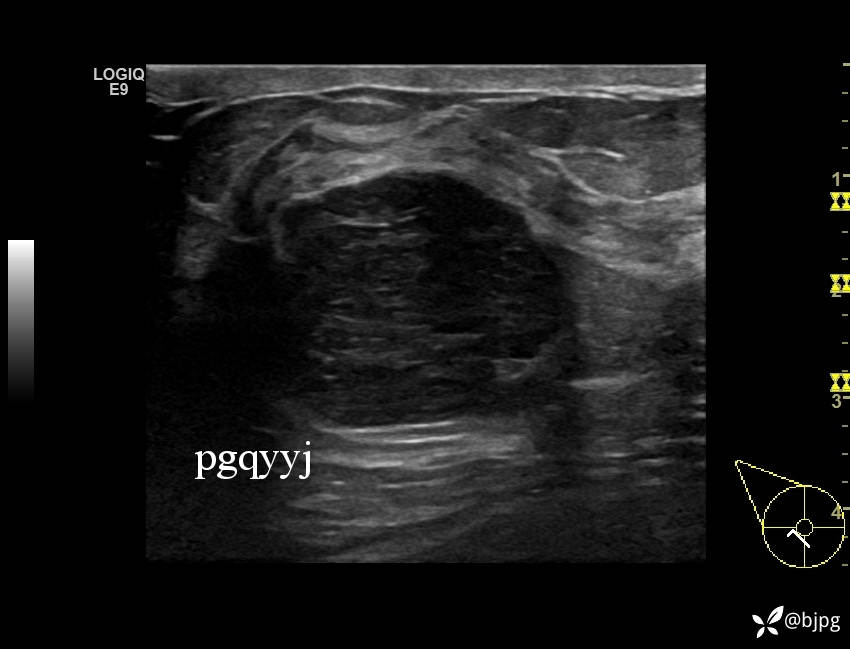

【患者信息】:女性36岁

【主诉】:发现右乳肿物一周

【检查】:超声

【临床诊断】:右乳结节,性质待定

【治疗经过及结果】:穿刺活检,欢迎同道讨论,穿刺病理数日后公布。

乳腺分叶状肿瘤 (7)